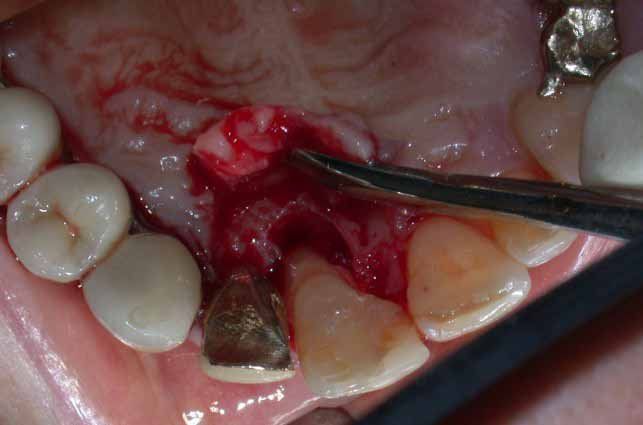

2° Caso: retrazioni gengivali